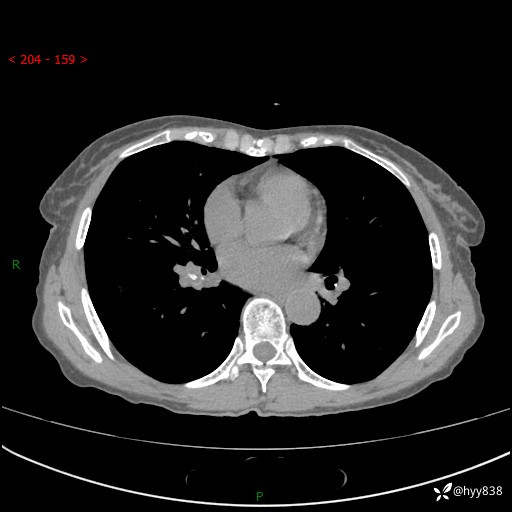

患者性别:男

患者年龄:69岁

简要病史:咳嗽咳痰2月,夜间加重

辅助检查:CT

临床诊断:感染

胸部CT平扫